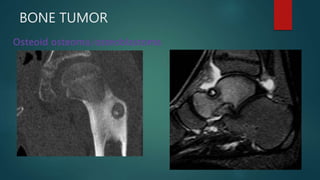

BONE TUMOR

Osteoid osteoma/osteoblastoma